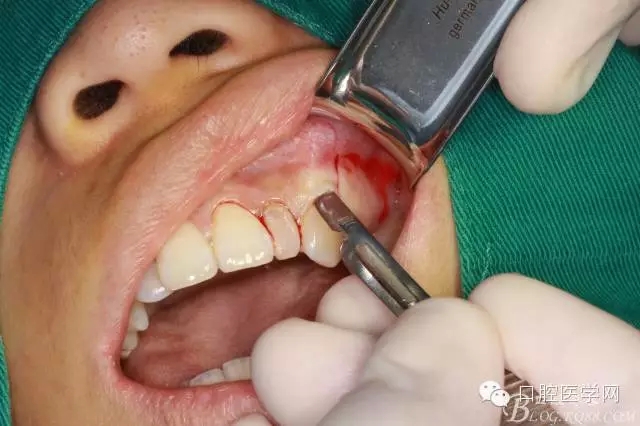

常規(guī)口內(nèi)外消毒鋪巾

局部浸潤麻醉

齦乳頭麻醉

鼻腭神經(jīng)麻醉

垂直切口

水平切口